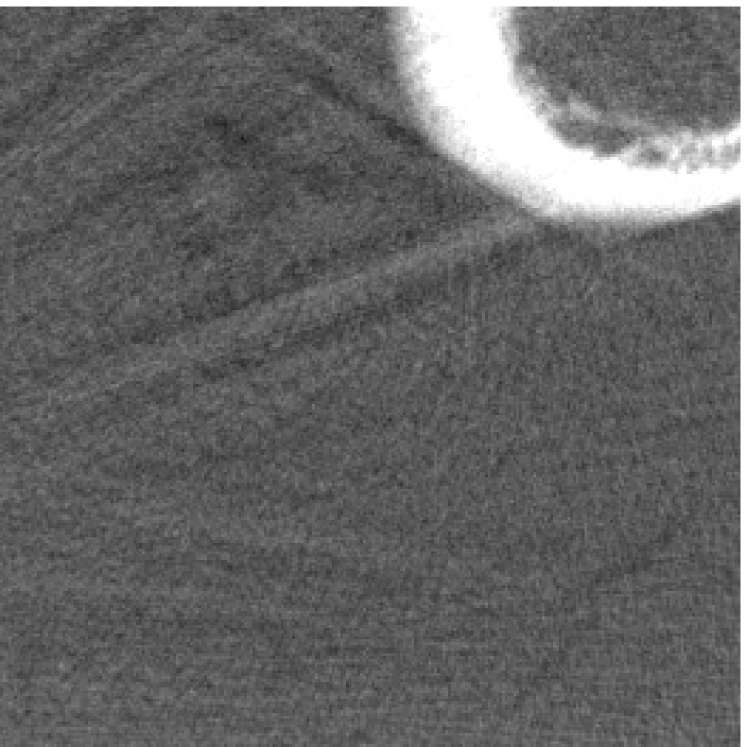

Figure 12 shows a comparison between the reconstructed image from NMAR and the unweighted JSR model. Figure 13 shows a comparison between the reconstructed images from TV-FADM and the proposed re-weighted JSR model. Zoom-in views are provided in both Figure 12 and Figure 13 for a better visual assessment. As one can see that the reconstructed images from the unweighted JSR model and TV-FADM are less noisy than NMAR as indicated by the blue ellipse curve, whereas NMAR does a better job in preserving image features and suppressing metal artifacts. However, there are also new artifacts around the metal on the right as shown in Figure 12(d). The proposed re-weighted JSR model has best overall performance in terms of feature preservation, noise and metal artifact reduction.